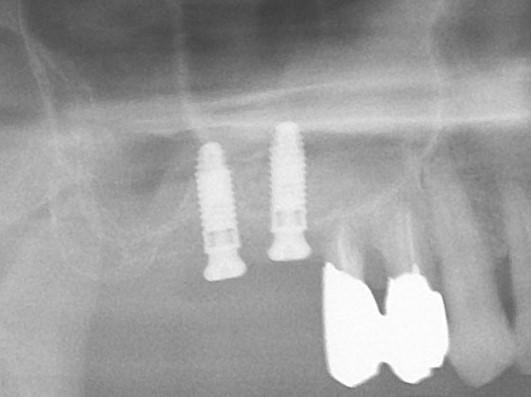

POI EXインプラント(京セラ) HA Tapered Bone level (カラーM) 埋入サイズ:直径4.2mm/長さ10mmを#25部位に埋入している。この時点ではガイドを用いたドリリングの後にフリーハンドで埋入を行っており、計画と若干のずれを生じる。現在の形になるまでの過渡期の症例である。

POI EXインプラント(京セラ)HA Tapered Bone level (カラーM) 埋入サイズ:直径4.7mm/長さ10mmを#27部位に埋入している。

#26部位にはすでにHA Tapered Bone level (カラーM) 埋入サイズ:直径4.2mm/長さ10mmが埋入されている。上顎洞の厚みがないことから、#15,17は1回法であるが、#26では2回法を選択している。上顎洞への脱落を防ぐためインプラント径より1mm大きいワイドカバーを装着している。この時点ではガイドを用いたドリリングの後にフリーハンドで埋入を行っており、計画と若干のずれを生じる。現在の形になるまでの過渡期の症例である。

最終補綴物装着時の口腔内所見

サイナスリフトを単独に行い、その後骨ができてからインプラント埋入手術を選択する術者も多いが、慎重に行えばワイドカバーなどを使うことで治療期間の短縮が可能となる。患者さんにとってはやはり、安全であれば早く、上部構造を入れて噛めるようにすることが重要である。その点では、同時埋入を積極的に行うことは良いと思うが、未熟な術者がサイナスリフト自体をするべきではないということを明記したい。

術後は良く噛めて機能面も十分に回復でき、患者さん自身も非常に喜ばれていました。他の不良補綴物や対側のインプラント治療も今後、行っていきたいとのことで、良かったと思っている。